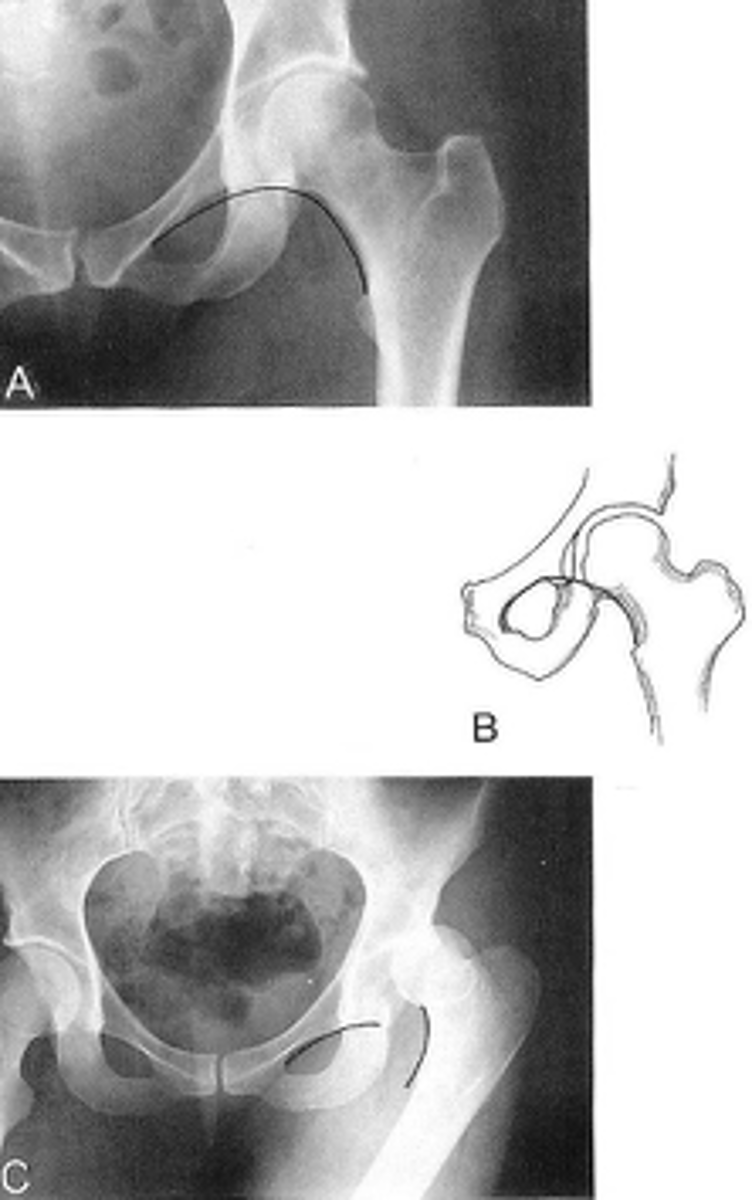

Shenton's line

ID measurement

<p>ID measurement</p>

- AP hip

- AP pelvis

What views are used to see Shenton's line?

<p>What views are used to see Shenton's line?</p>

- Smooth arc along femoral neck

- Obturator foramen

Shenton's line landmarks

<p>Shenton's line landmarks</p>

Continuous and smooth

Shenton's line normal measurements

<p>Shenton's line normal measurements</p>

- Hip dislocation

- Femoral neck fracture

- Slipped epiphysis

Clinical significance of Shenton's line

<p>Clinical significance of Shenton's line</p>